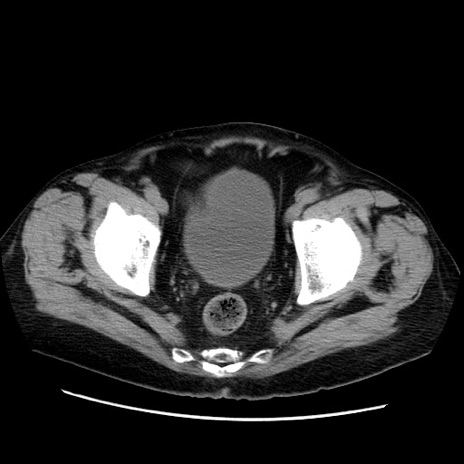

症例21(横断像)

【症例】70歳代男性

【主訴】腹痛

【現病歴】肝硬変・肝細胞癌にてかかりつけの方。約9時間前に食後より腹痛出現。症状が徐々に増悪し、嘔吐出現したため来院。

【既往歴】肝硬変、肝細胞癌(RFA、TACE後)

【身体所見】意識清明、表情苦悶様、BT 36℃、BP 129/78mmHg、P 88bpm、SpO2 97%(RA)、右上腹部から心窩部にかけて圧痛あり、反跳痛なし、筋性防御あり。

【データ】WBC 5800、CRP 0.16